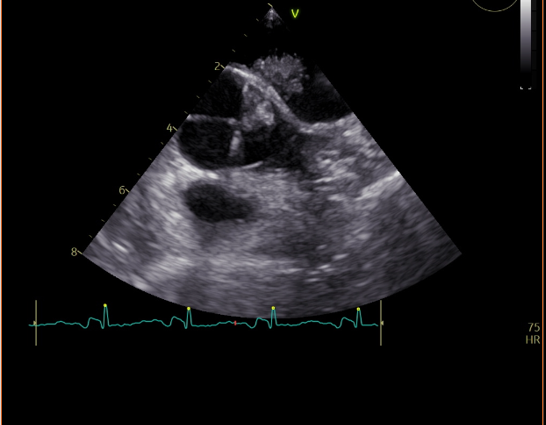

Inpatient evaluation: Transthoracic echocardiogram revealed ejection fraction (EF) of 55% and a bright mobile echogenic structure in the left atrium. Transoesophageal echocardiogram showed possible left atrial myxoma 1.3 cm x 0.96 cm. Multispecialty planning was initiated; cardiac surgeons offered her excision surgery to prevent further strokes (Figure 2a–2b­­).

Figure 2a Echocardiogram showing intra artrial mass.

Figure 2b Echocardiogram showing intra atrial mass separate from the valve.